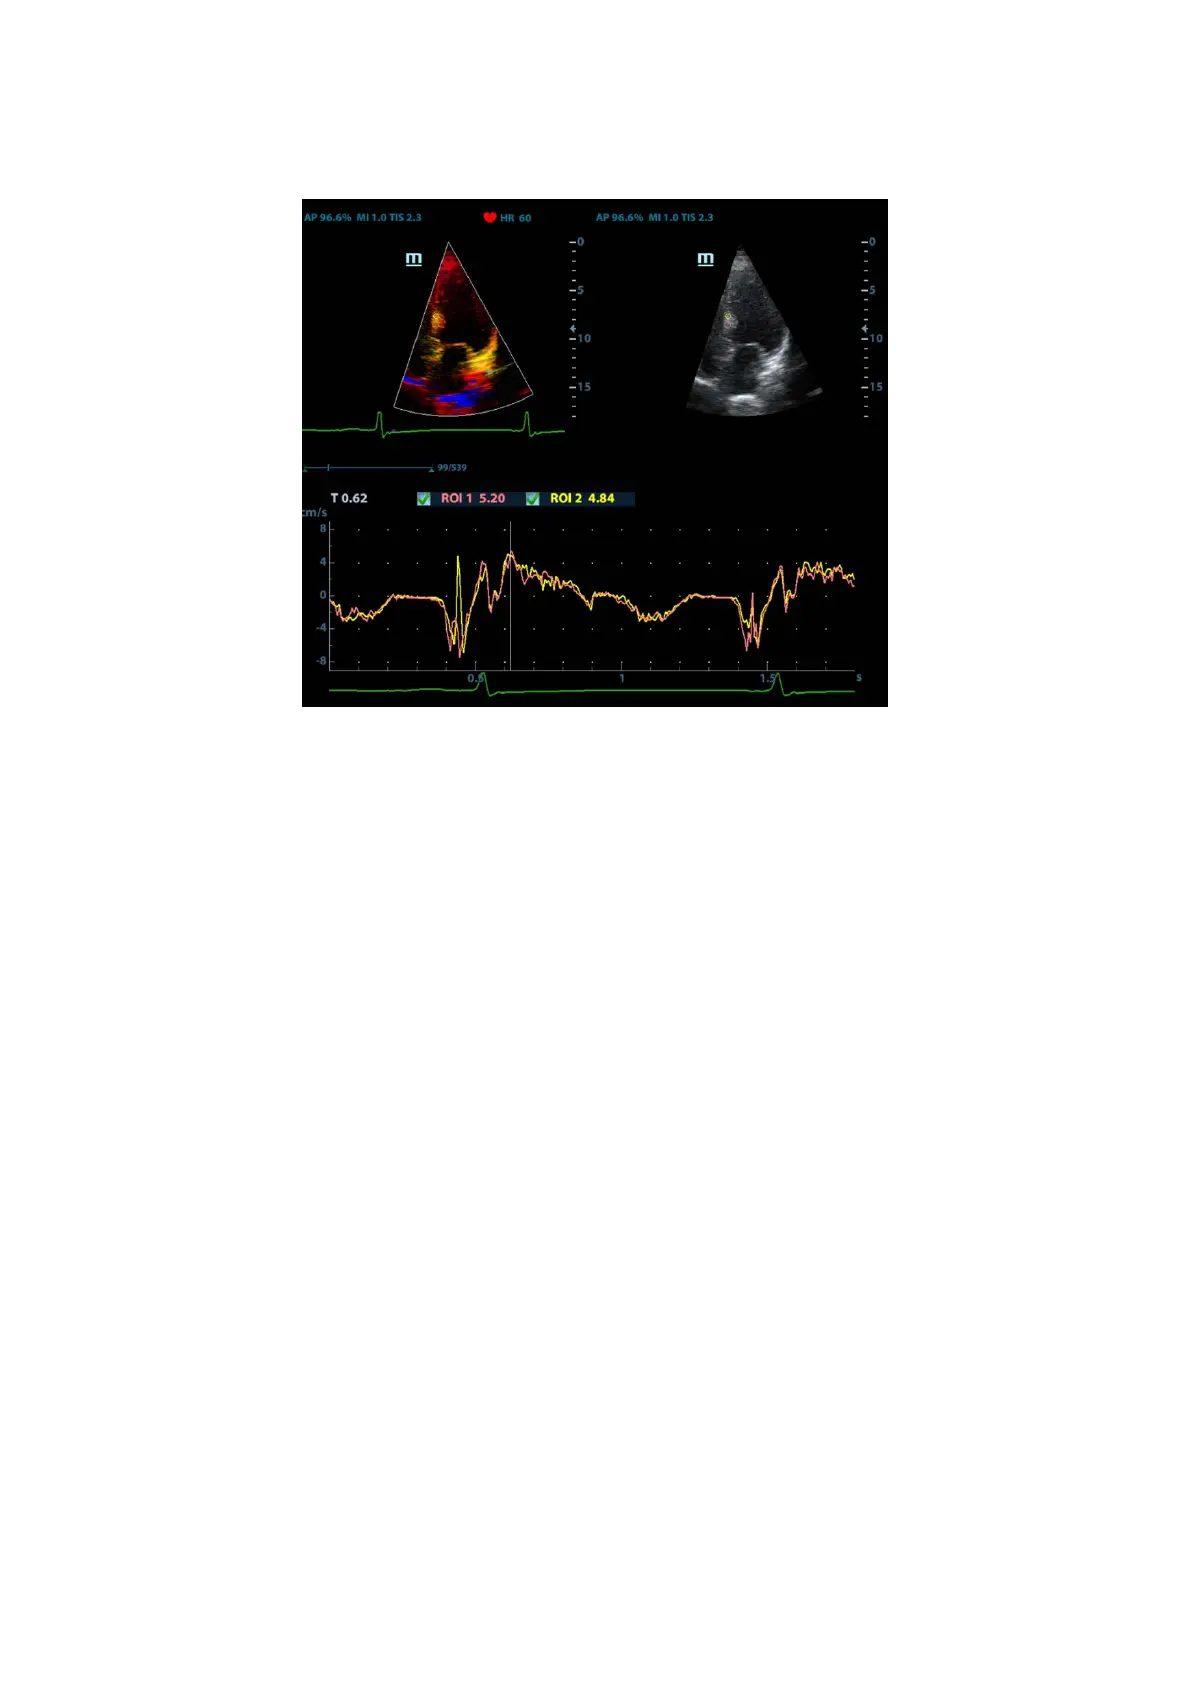

5.9.4.1 TDI QA Screen Description

TDI QA Screen

1 - TVI Cineloop window

Sample area: indicates the sampling position of the analysis curve. The sample area is

color-coded, 8 (maximum) sample areas can be indicated.

2 - B Cineloop window

3 - Displays the analysis curve

z The Y-axis represents the speed (unit: cm/s). [In the Strain Rate – Time curve,

the Y-axis represents the strain (%). In the Strain – Time curve, the Y-axis

represents the strain rate (1/s).]

z The X-axis represents the time (unit: s).

z Frame marker: a white line perpendicular to the X-axis which can be moved

horizontally left to right (and right to left) by rolling the trackball.

z Click the checkbox beside the ROI to set whether to hide or display the QA curve.

z You can get the current X/Y-axis value by moving the cursor onto one point on

the curve. If you press <Set> now, the frame marker will move to that spot.

4 - Displays the ECG trace (no ECG trace displayed here).

1

2

3

4